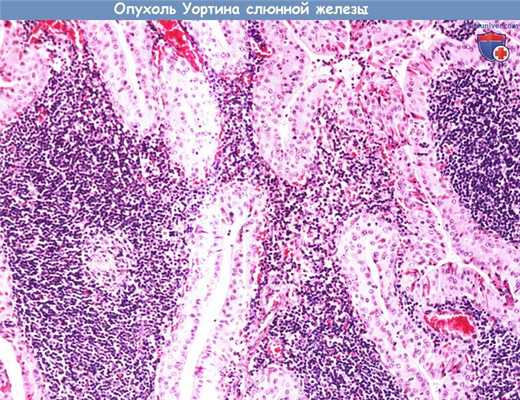

в) Опухоль Уортина (сосочковая кистаденолимфома). Составляя около 10% от всех новообразований слюнных желез, опухоль Уортина представляет собой вторую по частоте встречаемости доброкачественную опухоль слюнных желез. Из-за характерных гистологических свойств, более корректно называть данную опухоль «сосочковой кистаденолимфомой». Опухоли возникают только в околоушной слюнной железе, мужчины страдают в пять раз чаще, чем женщины. Предполагается, что разница в частоте встречаемости у мужчин и женщин объясняется тем, что определенную роль в патогенезе опухолей Уортина играет курение. В 10% встречаются опухоли обеих слюнных желез. В редких случаях могут становиться болезненными вследствие их аутоиммунного воспаления, которое развивается в ответ на лимфоидные клетки опухоли.

Опухоль Уортина имеет круглую или овальную форму, может быть гладкой, либо иметь дольчатое строение. Опухоль окружена капсулой. На срезе видна серая ткань, окружающая лимфоидную ткань белого цвета, а также множественные сосочковые кисты со слизью бурого цвета внутри. Благодаря такому строению опухоль и получила название сосочковой кистаденолимфомы. Рекомендуемое лечение — хирургическое удаление с сохранением лицевого нерва. Риск рецидива возрастает при удалении многодольчатых или двусторонних опухолей.

Опухоль Уортина (сосочковая кистаденолимфома) составляет примерно 3,5% всех эпителиальных опухолей слюнных желез.

Встречается практически исключительно в околоушной слюнной железе. Может иметь дольчатое строение, иногда двусторонняя.

При микроскопии опухоль имеет кистозно-сосочковое строение. Эпителиальные клетки с онкоцитарной метаплазией (большое количество цитоплазматических митохондрий,

розовая цитоплазма с частыми включениями) располагаются в два ряда, формируя сосочковые структуры, которые перемежаются с участками лимфоидной гиперплазии.

После удаления рецидивирует редко.